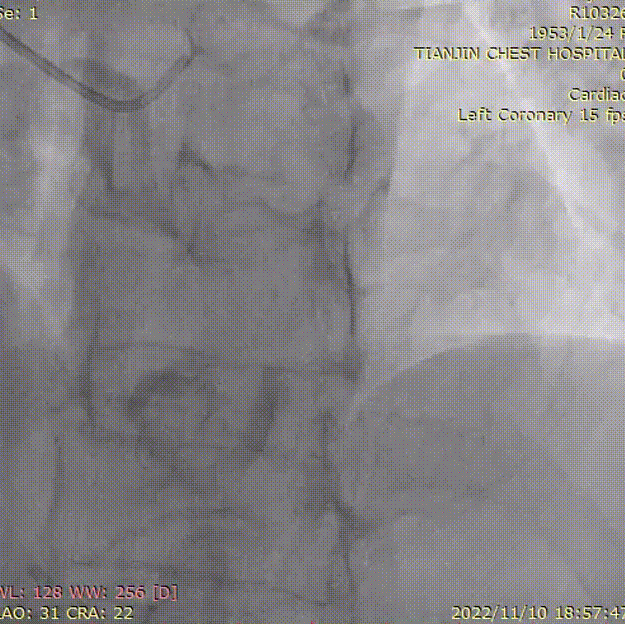

术中送6FXB3.5指引导管至左冠开口,送SION导丝通过LAD病变到达远端。行LADOCT检查示,病变长度为10.95mm,全程以纤维斑块为主,MLA1.77mm²,斑块负荷34%,全程未见TCFA、斑块破裂、钙化结节、血栓等高危斑块特征,近段参考直径为1.58 mm,远段参考直径为1.43 mm。

OCT影像

再次OCT检查示,“斜面旋切”棘突球囊预处理效果理想,可见多角度切痕,充分割裂阻力斑块,病变准备充分,MLA处纤维环打开,少量内膜撕裂,未见明显夹层、血肿。

OCT影像复查

术后造影显示LAD中段局部狭窄基本消失,远端血流TIMI 3级;术后再次行OCT示,MLA达到2.68mm²,管腔丢失明显改善,且无严重夹层、撕裂等形成,手术效果满意。

术后OCT复查